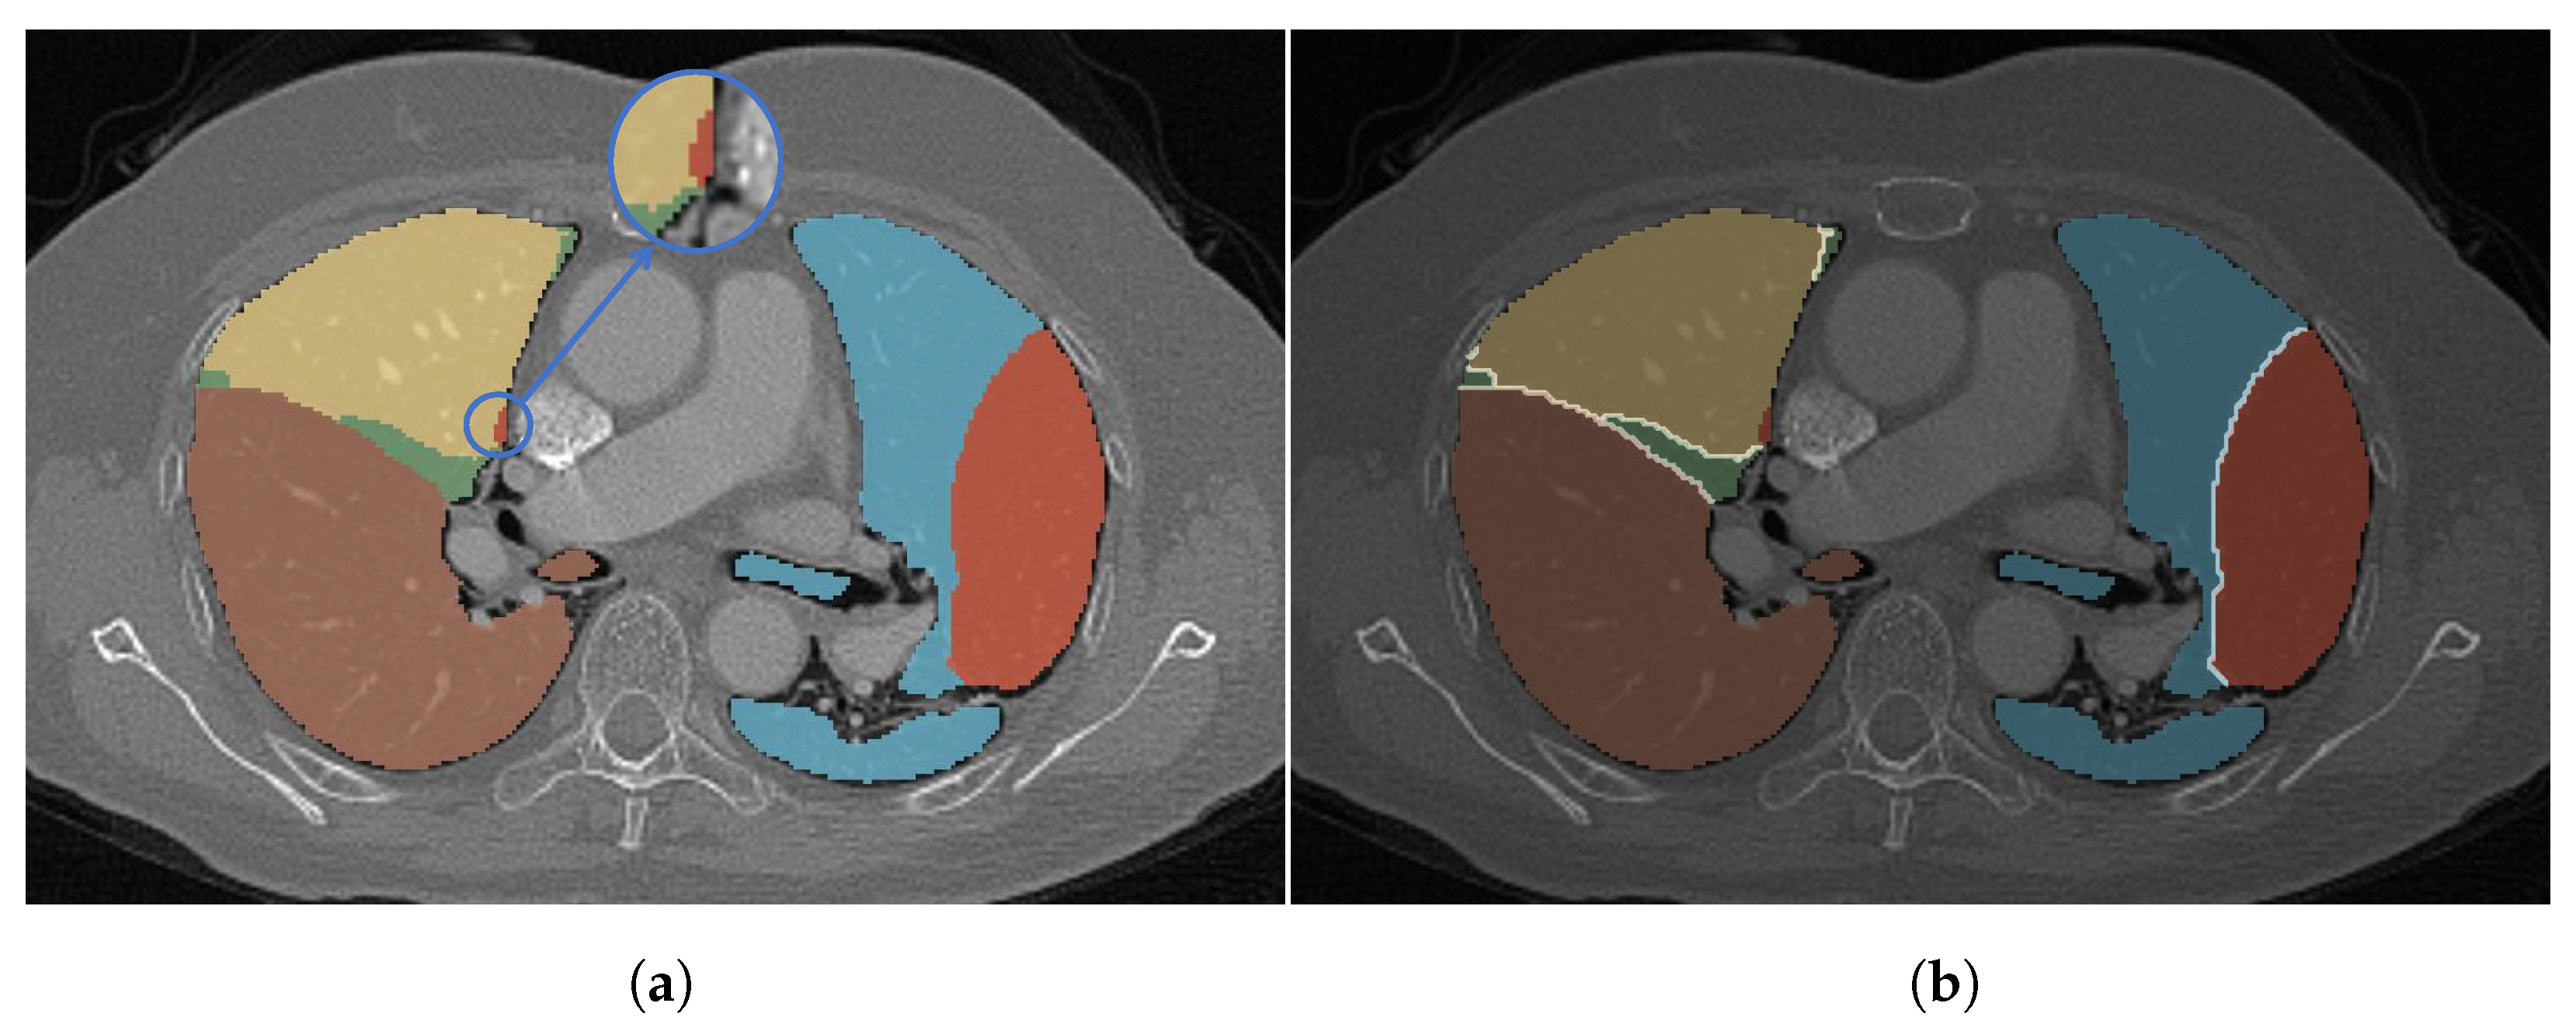

4.4. Qualitative Analysis